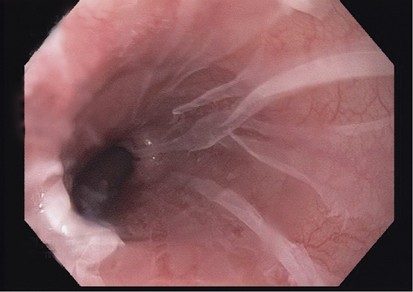

By definition, all patients in this study had endoscopic white plaques or membranes (Figures 1 and 2). The locations of the white plaques or membranes were specifically stated in the endoscopy reports of 26 of the 31 sloughing esophagitis patients (Table 2). Distal esophageal location for the endoscopic abnormalities was significantly more common than other sites (P<0.002). When the middle or proximal esophagus was involved, it was generally part of diffuse endoscopic abnormalities, rather than as localized disease. Additional endoscopic findings were infrequent and nonspecific, and included erythema beneath the white membranes in two patients, rings in two patients, distal narrowing in one patient, nodular mucosa in one patient, hiatal hernias in four patients, an irregular Z-line in one patient, and distal salmon-colored mucosa that was not biopsied in one patient. One additional patient had a large esophageal diverticulum containing pill fragments.